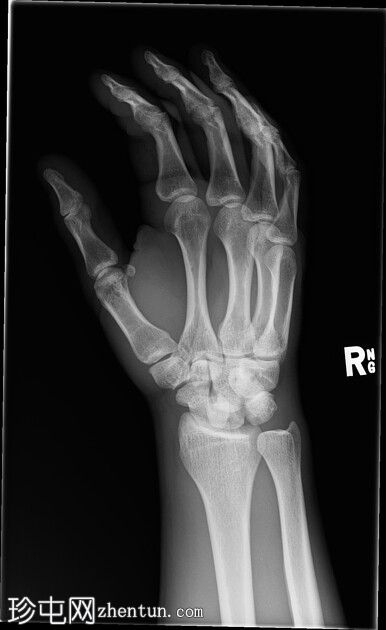

左腕

X光片

正面

斜位

侧面

前后位:舟月骨间隙明显增宽,月骨呈三角形。侧面显示月骨掌侧脱位,头状骨和桡骨远端保持正常排列,符合月骨脱位。陈旧性背侧三角骨骨折。腕部软组织肿胀。